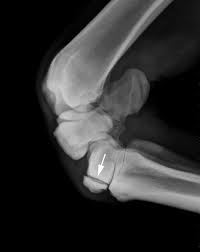

Triangular appearance of lunate on frontal projection. Slab fractures extend from one articular surface to another articular surface. An easy and convenient way to make label is to generate some ideas first. Of these 6 expensive faces , two, the anterior or palmar and the posterior or dorsal are rough and are related to the soft parts of the palmar and dorsal region. They are usually divided into two rows:

Carpi), are the eight bones of the wrist that form the articulation of the forearm with the hand. The term carpus is derived from the latin carpus and the greek καρπός (karpós). Triangular appearance of lunate on frontal projection. Study the carpal bones as pieces of a jigsaw puzzleleft: Capitate and all other carpal bones lie posterior to lunate on lateral radiograph. The carpus is a composite joint composed of all the articulations to which the seven carpal bones contribute. Occurs when the lunate maintains normal position with respect to the distal radius while all other carpal bones are dislocated posteriorly. The carpal bones are the eight small bones that make up the wrist (or carpus) that connects the hand to the forearm. An easy and convenient way to make label is to generate some ideas first. The carpal bones are the eight bones of the wrist that form the articulation of the forearm with the hand. If an abnormal alignment of the carpal bones is depicted during imaging of the. Articulates with ulnar carpal bone. Dynamic instability is present if the carpal bones appear normal in standard radiographs taken at rest, but abnormal movement is identified in clinical examination, radiographic stress views, or cineradiography.

Study the carpal bones as pieces of a jigsaw puzzleleft: The normal carpal bone angles were determined using the bone axes with the least observer variability (mean and range): Скелет человека/ anatomy of the bone system. Occurs when the lunate maintains normal position with respect to the distal radius while all other carpal bones are dislocated posteriorly. The change in the third carpal bone is seen on a skyline radiograph as increased radiopacity of the radial fossa. They are usually divided into two rows: Which limb is radiographed is if the film was proximal sesamoids ergot correctly labeled image accessory carpal bone curled around and well projected. View carpal bones research papers on academia.edu for free. The carpal bones are the eight bones of the wrist that form the articulation of the forearm with the hand. Osteochondral fractures (carpal chip fractures) of the carpal bones are a common cause of lameness in racehorses. Log in through your library. Triangular appearance of lunate on frontal projection. In the carpus, slab fractures.